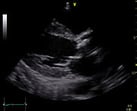

心臓超音波検査(心エコー)とは、人の耳には聞こえないほどの高周波数の超音波を心臓に発信して、返ってくる反射波を受信し、心臓の様子を画面に映し出して診断する検査です。

リアルタイムでの心臓の大きさ、筋肉の壁の厚さや動きを観察します。また、心臓内の血液の流れを計測することで心機能の評価が可能です。

患者さんに苦痛をあたえずに、心臓の各部位の形や大きさの異常、動きの異常を簡単に診断できます。種々の心臓病の診断、重症度の評価、治療効果の判定など幅広い目的で検査されます。

心臓に穴が開いていないか、心臓の中にある弁(扉)から血液が逆流していないかなど検査します。